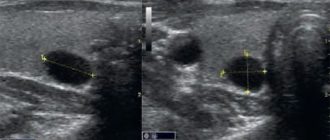

УЗИ щитовидной железы, киста правой доли

Киста левой доли щитовидной железы Очень часто правильное диагностирование патологий в щитовидной железе представляет